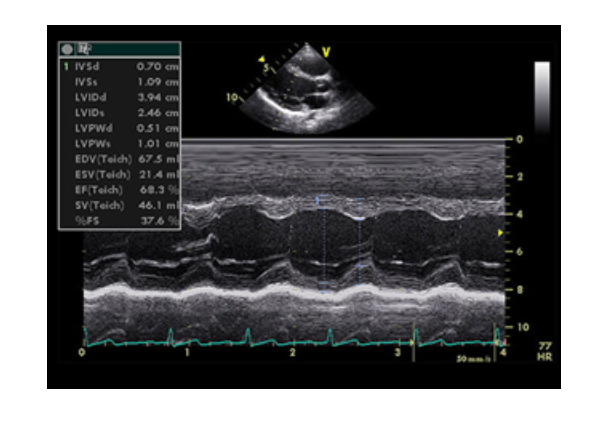

2. Siêu âm tim kiểu TM (Còn gọi là M mode)

Vì tim vận động liên tục theo chu kỳ tâm thu và tâm trương, các van tim cũng vậy, nên khi quét chùm tia siêu âm đi qua 1 thành phần giải phẫu của tim theo 1 vận tốc nhất định, ta sẽ thu được hình ảnh của thành phần đó có dạng sóng. Với kiểu TM, do định vị được các thời điểm trong chu chuyển tim: tâm thu, cuối tâm thu, tâm trương, cuối tâm trương nên việc đo các kích thước và chức năng co bóp của tim rất chính xác. Các lát cắt chủ yếu trong siêu âm tim M mode là lát cắt trục dọc cạnh ức trái..., dựa trên hình ảnh 2D, trục ngang cạnh ức trái, dịch chuyển thanh định hướng (cursor) tới vị trí cần khảo sát để thu được hình ảnh tim mạch.

Siêu âm tim kiểu TM, lát cắt trục dọc cạnh ức trái, cursor ỏ sát đầu tận cùng van hai lá, đo được đường kính thất trái cuối tâm trương (LVIDd), đường kính thất trái cuối tâm thu (LVIDs), qua đó tính chức năng tâm thu thất trái (EF). Ngoài ra còn đo được kích thước thất phải, độ dày của thành thất trái ở tâm trương (IVSd và LVPWd) và tâm thu (IVSs và LVPWs).